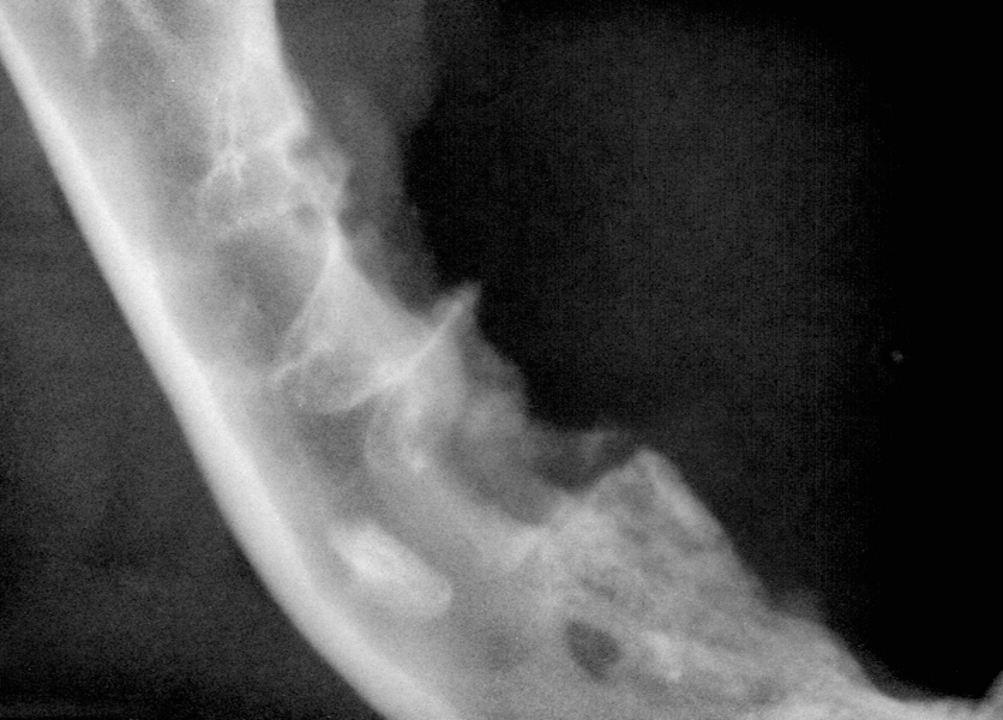

The first point is to NEVER attempt to extract a root blind. Fishing down an alveolus for a retained root is almost never successful and often results in forcing the root into the nose or mandibular canal. (Figure 1).

This is because there is incomplete apical bone coverage in many cases, especially the premolars and molars of small-breed dogs.

The first step is to obtain radiographs to evaluate the retained roots. This will inform you of the amount of root left, as well as its positioning in relation to the vital structures. Next, create a mucogingival flap (we generally recommend an envelope flap (Figure 2).